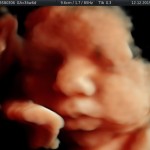

- Crecimiento fetal.

- Las estructuras anatómicas fetales: diagnóstico de Malformaciones Estructurales de aparición tardía (displasias esqueléticas, alteraciones cardiacas pequeñas, alteraciones la vía urinaria y obstrucciones intestinales.